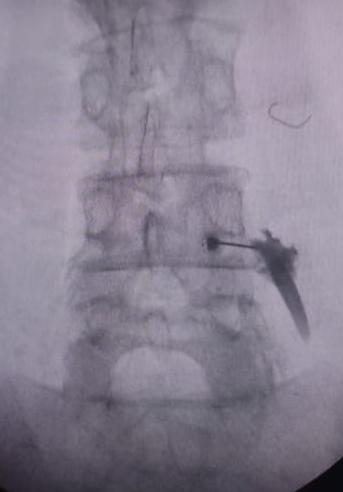

Leg Pain due to Spine issues? Not Responding to Me...

View Details

Spine Surgery is too risky !!. Spine Surgery gets ...